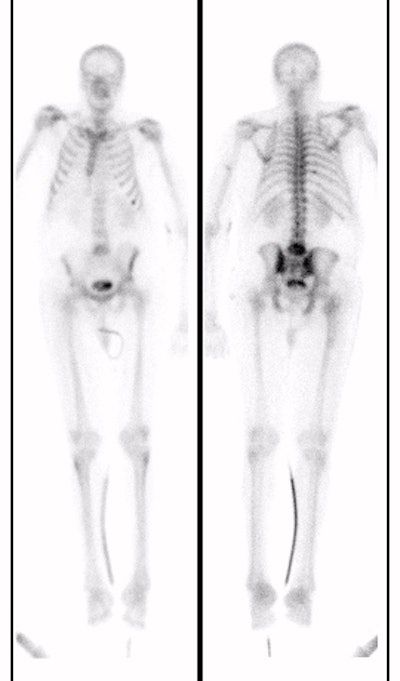

(Case submitted by Dr. Marc Cote, D.O.)The case below illustrates the decreased sensitivity of In-111 WBC imaging for the detection of vertebral osteomyelitis. The whole body bone scan revealed increased tracer activity within L5. The In-111 WBC exam (shown below with Tc-MDP exam for comparison) demonstrated no evidence of increased tracer accumulation in L5 (blue arrow).